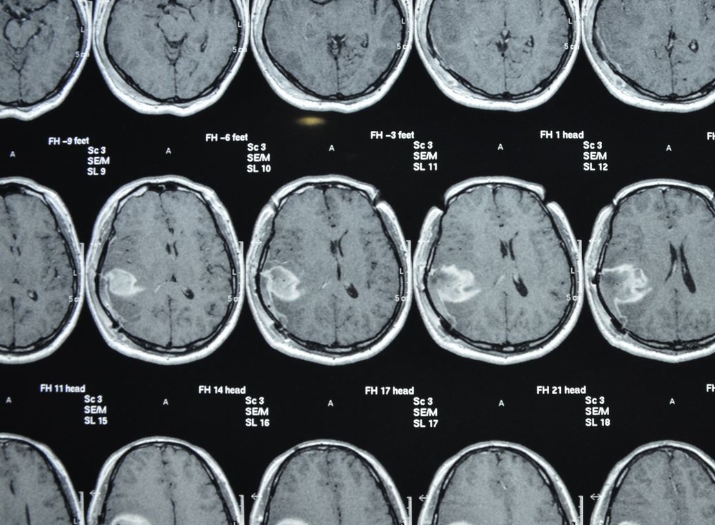

诊断:一般需要结合临床症状、影像学检查(如头颅磁共振成像、计算机断层扫描等)以及病理检查来明确诊断;